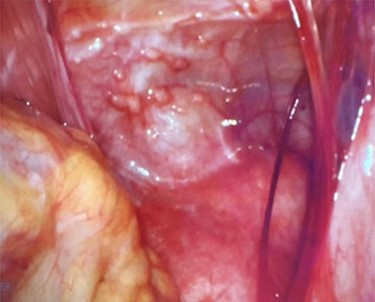

Abdominal wall anterior to the uterus with scattered peritoneal nodules.

On entering the abdomen, the terminal ileum and cecum were grossly normal, while the right ovary showed papillary excrescences on the serosal surface (Fig. 3). The appendix was proximally distended with distal serosal injection and chronic scarring into the pelvis (Fig. 3). An appendectomy was performed (Fig. 5A). Scattered peritoneal nodules were visualized on the abdominal wall anterior to the uterus (Fig. 4), and several biopsies were taken. Cut sections of the appendix revealed uniformly firm, white tissue throughout the entire specimen with a possible centrally located, pinpoint lumen, suggesting fibrous obliteration. No well-circumscribed lesion was identified; however, histopathology showed the appendiceal wall was diffusely expanded by an irregular, wavy spindle cell proliferation involving the mucosa, submucosa, muscularis propria and subserosal tissue (Fig. 5B and C). Immunohistochemical stains highlighted a mixture of S100/SOX10-positive cells and CD34-positive cells, consistent with appendiceal neurofibroma (Fig. 5D). Pathologic diagnosis of the peritoneal biopsies was low-grade serous neoplasia.